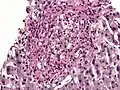

Histoplasma. PAS diastase stain.

Histoplasma in a granuloma. PAS diastase stain.